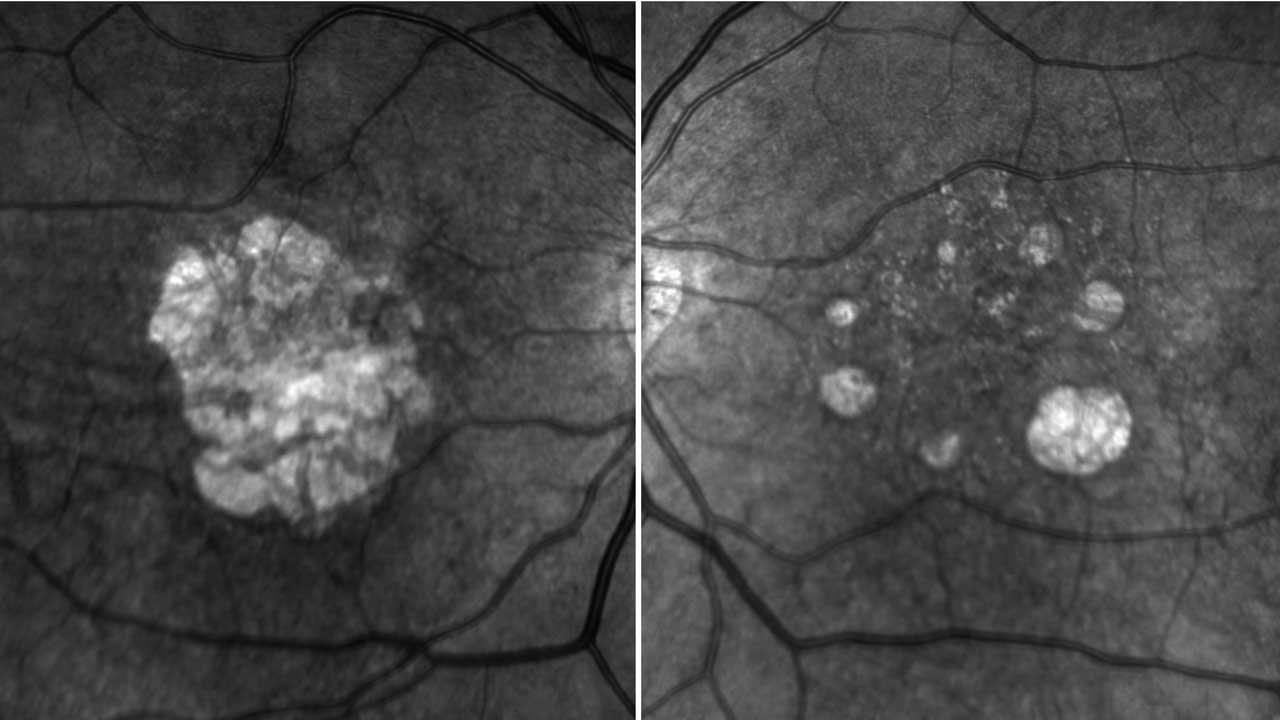

JNJ-1887 (Janssen) is a one-time intravitreal injection being studied for the treatment of GA. The goal of treatment is to increase the expression of the soluble recombinant version of CD59. CD59 inhibits the membrane attack complex formation, the terminal step of complement-mediated cell lysis, and can help protect retinal cells. A Phase 1 study of 17 GA patients treated with JNJ-1887 showed promising efficacy measures for patients receiving higher doses with a continual decrease in lesion growth over 6-month intervals.7 A Phase 2 PARASOL trial is enrolling.